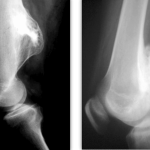

Η απεικόνιση των βλαβών πρέπει να κατευθύνεται από τον Ορθοπαιδικό Χειρουργό και ακολουθεί μία συγκεκριμένη μεθοδολογία.